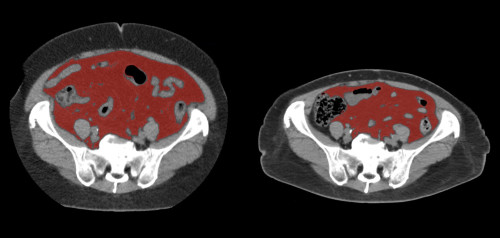

④

50代・男性(ご本人のご厚意で画像提供)

治療内容:チルゼパチド7.5mgの週1回自己注射による脂肪減少と脂肪肝改善

治療期間: 12ヶ月(52週)((用量は2.5mgから開始し最大で15mg。減量効果が得られる必要用量には個人差があります。))

費用:自由診療の場合は9900円(税込)×52(週)=514800円

想定されるリスク・副作用:下記に副作用を記載

※医療広告ガイドラインに準拠して表記

1:脂肪の減少

皮下脂肪の減少(赤色部分)